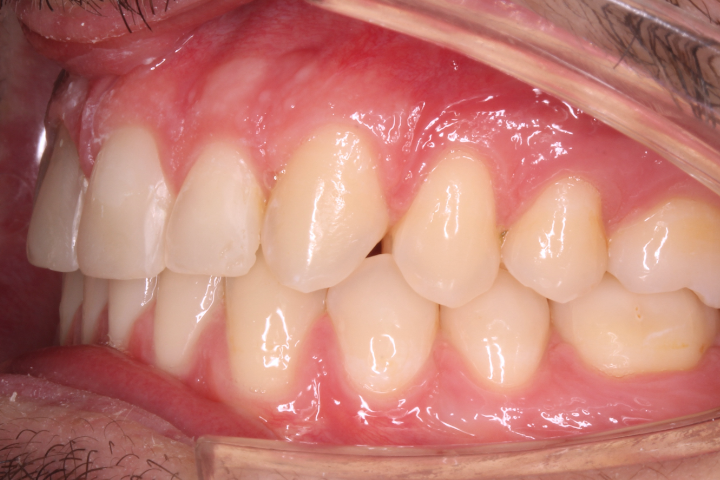

Trattato una decina d’anni or sono si è intervenuti dopo esposizione chirurgica ad aggancio di due elementi tramite bottoni, legature metalliche ed elastico.

Riportati i canini all’interno dell’arcata l’occlusione è stata strutturata con apparecchiature fisse; il ricorso a resine composite ha migliorato l’estetica dell’incisivo traumatizzato.